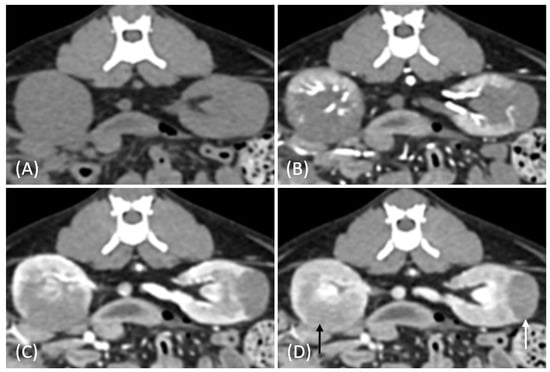

Figure 7.

(A) Pre-contrast and (B) late nephrographic/early excretory phase contrast-enhanced computed tomography (CT) images of a renal cell carcinoma (RCC). The image shows a large renal mass with rim enhancement and no internal enhancement. Vascular structures such as the aorta (white arrow) and CVC (black arrow) are visible; however, the renal artery and vein are not clearly identifiable. Tumor invasion into adjacent musculature is observed (arrowhead).